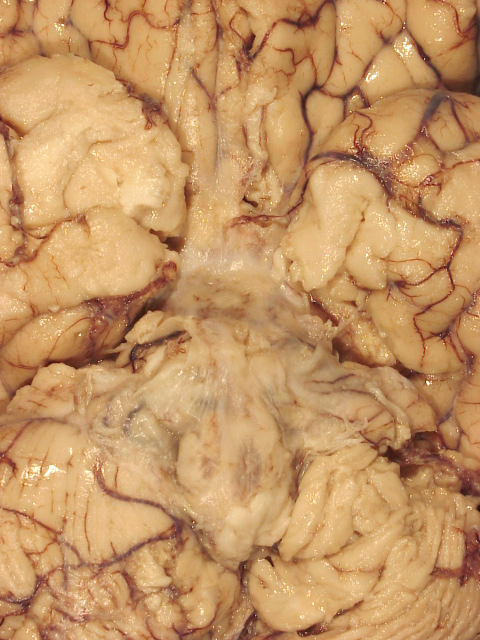

Cryptococcus is an oval yeast about the size of a red cell, surrounded by a gelatinous capsule. There are several species of cryptococcus. The most common, cryptococcus neoformans, causes 95% of infections. It is a worldwide fungus, present in bird droppings, vegetables, and soil. It may affect healthy individuals but is particularly common in immunodeficient patients, especially patients with HIV/AIDS. It is most often community-acquired. The portal of entry is the respiratory tract but pulmonary infection may be asymptomatic or minimally symptomatic. Cryptococcus spreads to the brain from the lungs and often causes meningitis without involving other organs. In the CNS, cryptococcus grows extensively in the subarachnoid space and perivascular spaces, which become cystically distended to the point that brain sections look like Swiss cheese. In immunosuppressed individuals, inflammation is absent or mild. In immunocompetent hosts, cryptococcus elicits a cell-mediated immune reaction with lymphocytes and epithelioid cell granulomas. Rarely cryptococcus may cause mass lesions (cryptococcomas). Cryptococcus meningitis has an insidious onset and may go on from weeks to years. It can cause hydrocephalus, dementia, cranial neuropathies and focal neurological deficits. The CSF in cryptococcosis shows mononuclear pleocytosis, elevated protein, and low glucose, similar to tuberculous meningitis. Yeasts can be identified by microscopy of the CSF and their antigens can be detected by latex agglutination.